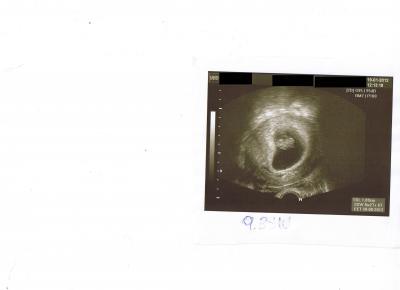

Huhu Zusammen! Hab's gestern nimmer ganz geschafft, weil mein großer so schlecht geschlafen hatte und ich das mit dem einscannen der Bildchen net so schnell hin bekam. Beim FA war alles super. Baby hatte die Beinchen erst überkreuzt und die Händchen am Kopf. beim Vermessen hat's dann kräftig gestrampelt, hat ihm wohl nicht so ganz gepasst. Mein Hb ist bei 11,5 bin ich soweit ebenfalls zufrieden damit. Hoffe das er in dieser Schwangerschaft nicht wieder so weit absinkt. Zugenommen hab ich nur erstaunlich wenige 800gr. freut mich auch mal. :-) Bei meinem Sohn hab ich 15kg in der Schwangerschaft zugenommen, mal sehen wieviel es dieses mal noch werden. Unser Sohn inklusive Papa, waren super begeistert von dem Zwerg und unser Kleiner hat das US-Bildchen erstmal nicht aus der Hand gegeben mit dem Baby *g* In vier Wochen am 15.3. ist dann der nächste Termin. Bildchen hänge ich an. Liebe Grüße Traeummaus

dankeschön! Achso, der Bauchzwerg is schon 6cm groß :-) hatte ich ganz vergessen zu schreiben. hihi